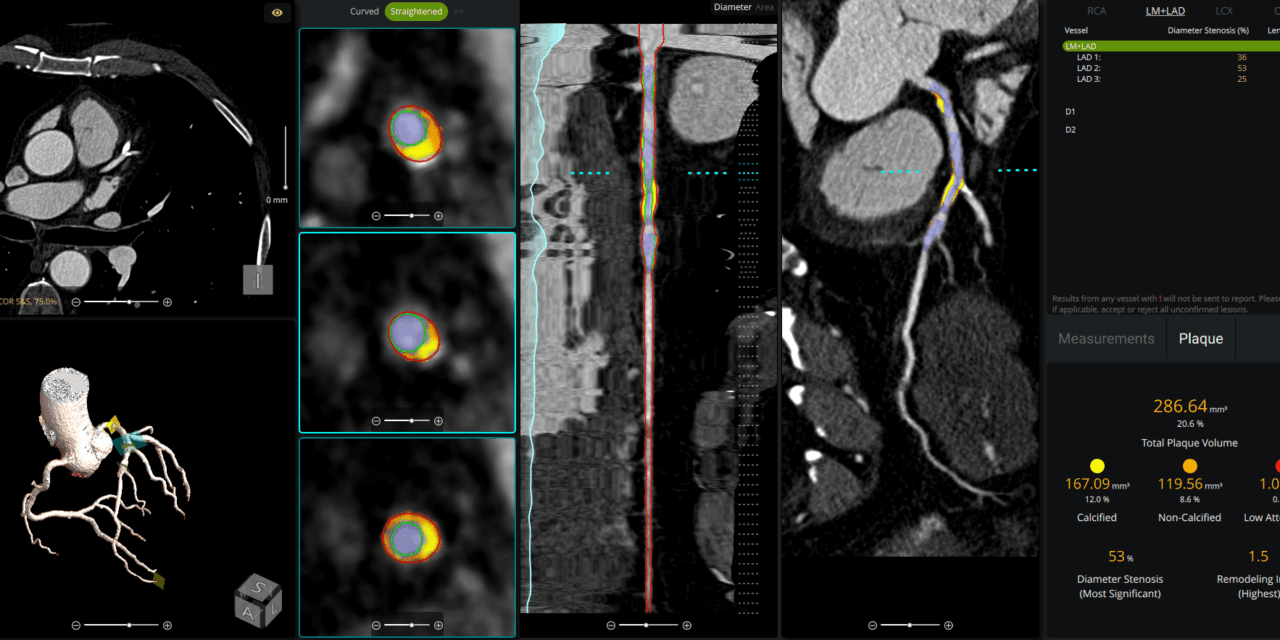

The clearance enables on-premise AI analysis of coronary CT angiography for quantifying calcified and non-calcified plaque.

Circle Cardiovascular Imaging (Circle CVI), specializing in cardiovascular imaging solutions, announced that its cvi42 | Plaque solution has received 510(k) clearance from the US Food and Drug Administration (FDA) and is now available for clinical use in the United States. The AI-enabled solution allows clinicians to perform coronary plaque analysis on-premise.

The AI-enabled technology within cvi42 | Plaque is designed to deliver fast, accurate, and reproducible results for quantifying total, calcified, and non-calcified plaque. This analysis aims to more precise risk stratification and helps inform personalized treatment plans.

Photo caption: cvi42 | Plaque

Photo credit: Circle CVI